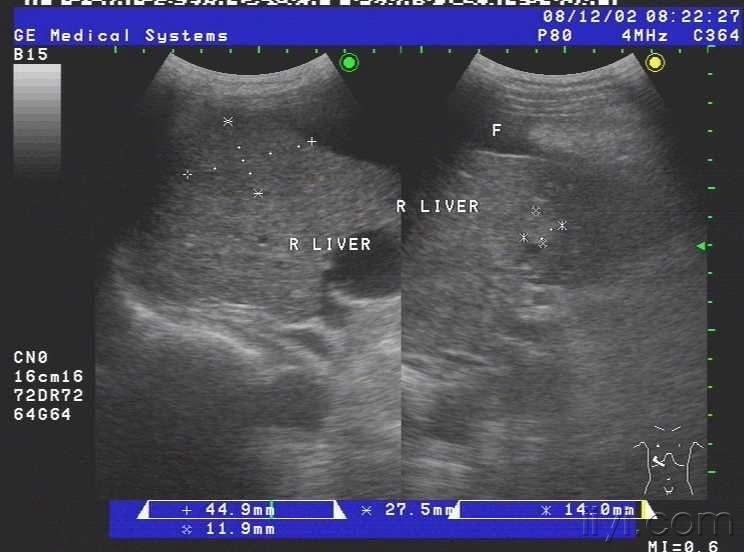

患者女,69岁,病毒性肝炎病史三年余,近半月自觉腹部胀满,来我院就诊,超声查示肝脏被膜不光滑,呈锯齿样,肝内回声不均匀,肝内多发小中等偏强回声团块,大小约1.5cm-3.0cm不等,无明显包膜,境界较清,另于肝右前叶近肝表面见一个大小约4.5cmx2.4cm的椭圆形实性低回声团块,至此处被膜略隆起,团块无明显包膜,伴侧方声影,后方回声增强,内部回声均匀,CDFI未见血流信号.右叶内另见两个类圆形囊性无回声区,肝内管道结构显示不清,肝门脉主干内径约1.1cm.胆囊壁厚1.0cm,囊内透声尚可,脾脏轻度增大,脾门脉无扩张;平卧位腹腔扫查于肝上前间隙肝肾隐窝脾肾隐窝双髂窝均见液性暗区.超声提示:1.肝硬化肝内多发实性团块合并胆囊炎脾轻大及大量腹水;考虑不除外肝癌?